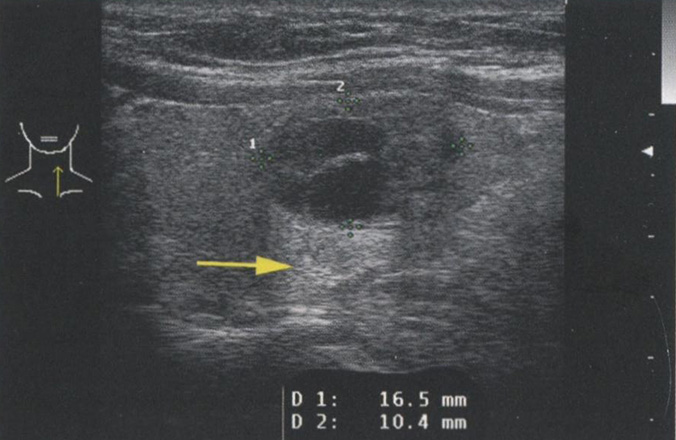

Однако усиление сигнала происходит не только при наличии кистозных узлов. Любая структура, вызывающая минимальное затухание УЗ-сигнала, будет иметь усиление кзади от себя. На рис. 2.13 продемонстрировано усиление сигнала кзади от солидной аденомы ПЩЖ. На рис. 2.14 показано усиление сигнала позади доброкачественного коллоидного узла. Из-за высокого содержания жидкости и коллоида в узле и, как следствие, уменьшения клеточного компонента затухание сигнала в этом образовании происходит в меньшей степени, чем в окружающей ткани щитовидной железы.

Рис. 2.14. Усиление сигнала. Этот доброкачественный коллоидный узел содержит много жидкости и коллоида, что приводит к уменьшению клеточного компонента. Сниженное затухание сигнала в узле обусловливает усиление сигнала, несмотря на то что этот узел является солидным